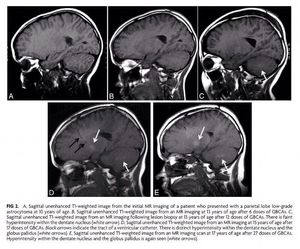

Pediatric Patients Demonstrate Progressive T1-Weighted Hyperintensity in the Dentate Nucleus following Multiple Doses of Gadolinium-Based Contrast Agent. Roberts DR et al. AJNR December 2016